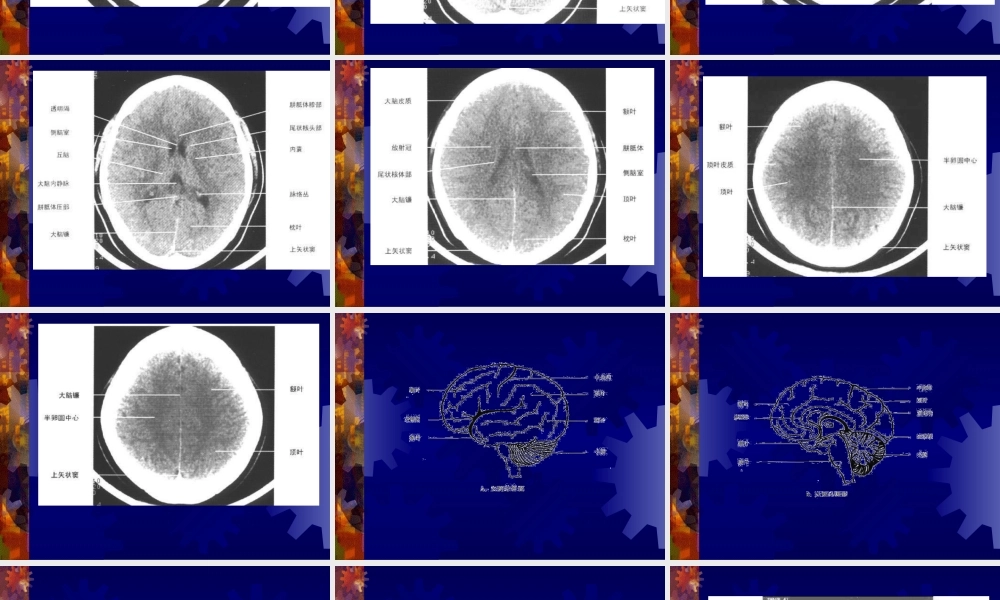

正常头颅CT及MRI解剖闫炳苍一、头颅CT正常解剖二、正常头颅MRI解剖三、脊柱的正常MRI解剖